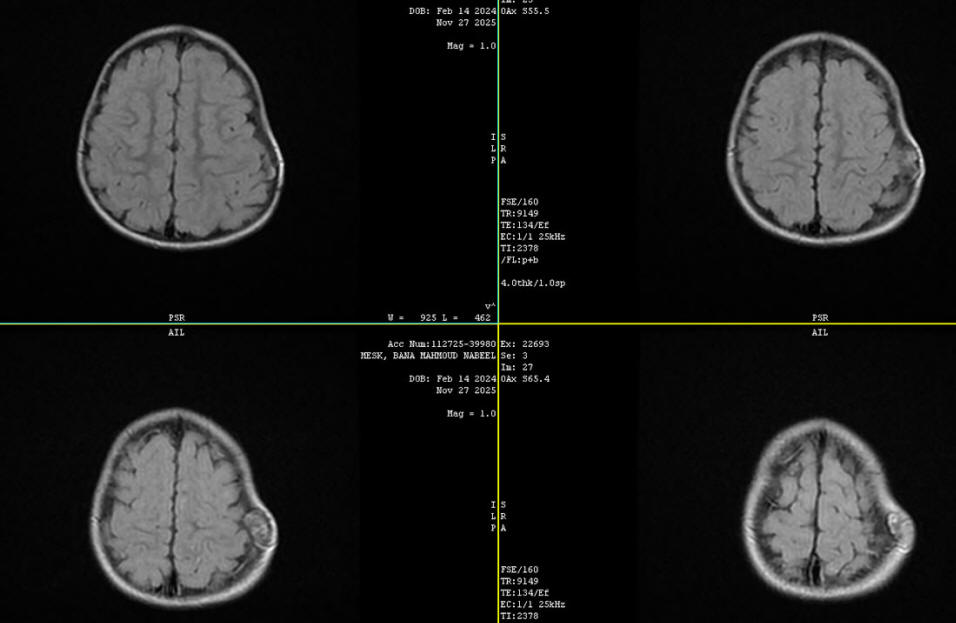

17-DECEMBER-2025 BANA MAHMOUD MISK

1.9 YEARS INTRAOSSAL LANGERHANS TUMOR IN THE LEFT PARIETO-OCCIPITAL

REGION.

The patient brought to the clinic

16-December-2025 with family, telling that a subgalial mass

is progressing in the left parieto-occipital

region. MRI done 27-November-2025 showing the

mass. |